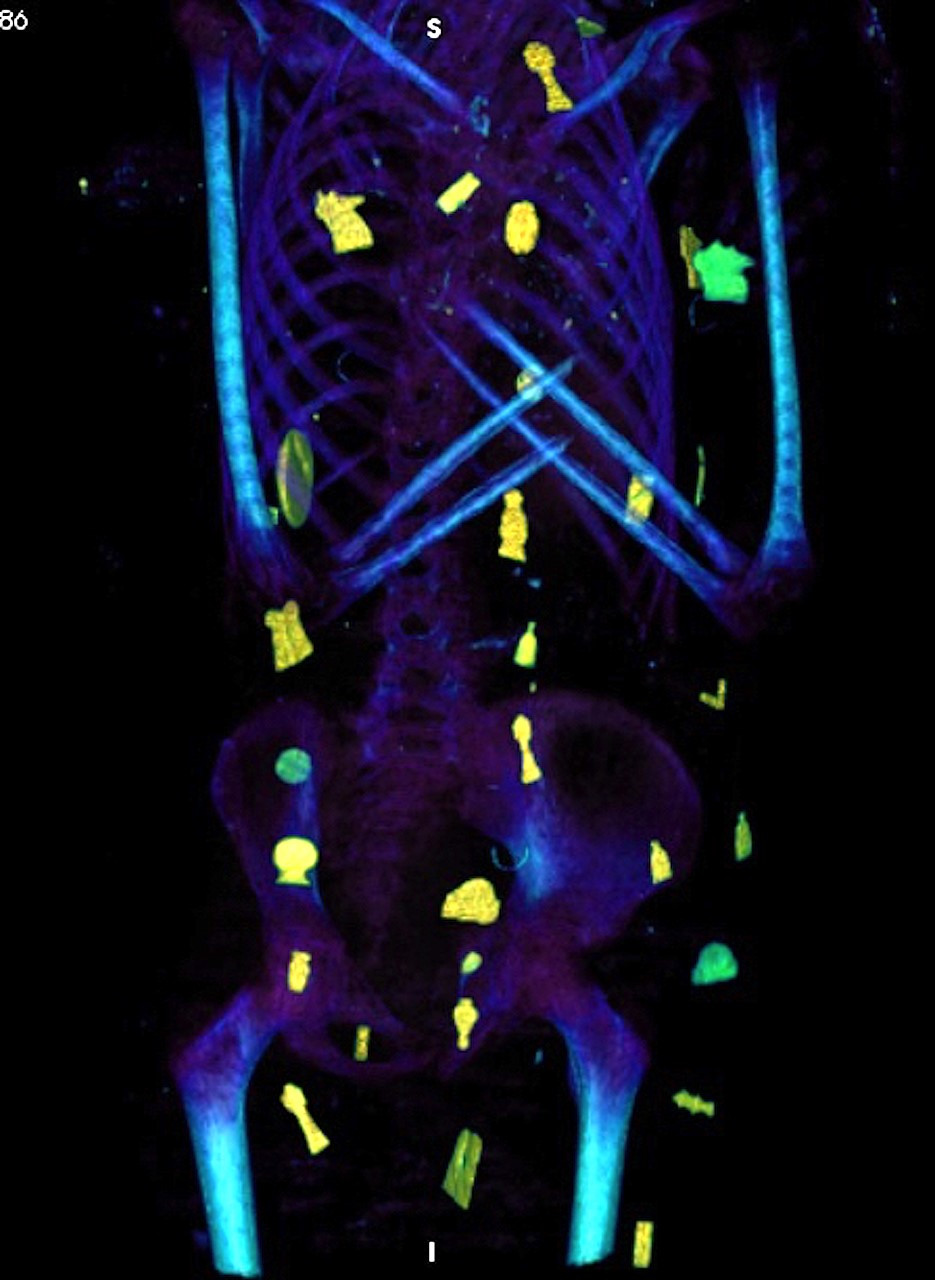

كما أوضحت صور الأشعات المقطعية الثنائية والثلاثية الأبعاد عن وجود حوالي 49 تميمة مرتبة ترتيبًا منمقًا في ثلاث أعمدة بين طيات اللفائف الكتانية وبداخل تجويف المومياء. كما أظهرت الأشعة أيضا 21 شكلًا مختلفًا للتمائم مثل عين المعبود حورس والجعران وتميمة الأفق والمشيمة وعقدة إيزيس والريشتان، وغيرهم.

ومن خلال نتائج قياسات الأشعة تبين أن 30 تميمة من التمائم المكتشفة داخل المومياء صنعت من الذهب بينما باقي التمائم صنعت من الأحجار أو الفيانس، بالإضافة إلى تميمة علي شكل لسان من الذهب وضعت بداخل فم المتوفي ليتمكن من التكلم في العالم الآخر، كما يوجد تميمة على شكل أصبعين أسفل الجذع لحماية فتحة التحنيط، وتميمة أخرى كبيرة من الذهب لجعران القلب موجودة بداخل تجويف صدر المومياء، والذي تم عمل مستنسخ منه باستخدام الطباعة ثلاثية الأبعاد.